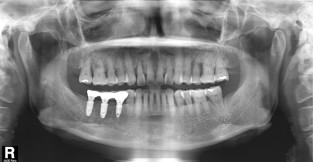

전체어금니

치료기간 : 2022-03-05 ~ 2022-10-01

1. 상기 x-ray 이미지 모두 동일한 해당 의료기관에서 진료한 환자입니다.

2. 상기 x-ray 이미지 모두 동일 인물의 것입니다.

3. 치료 전 이미지는 2022-03-05에 촬영했으며, 치료 후 이미지는 2022-10-01에 촬영하였습니다.

4. 상기 x-ray 이미지 모두 동일 조건에서 환자분의 동의를 받아촬영되었습니다.

* 임플란트 시술은 환자분의 상태(고혈압, 당뇨 등)에 따라 부작용이 있을 수 있으니, 반드시 전문의와 상담이 필요합니다.

* 임플란트 수술 부작용

: 수술 후 출혈, 교합, 통증, 붓기, 염증 등의 문제점이 발생할 수 있습니다.)

* 본 이미지들은 의료광고법을 준수하여 게시하였으며, <의료법 제 56조 제2항 제7호>에 의거하여 개개인의 신체 상태와 질병 진행도 등 여러 요인에 따라 치료 효과가 상이하기에 진료계획 또한 달라질 수 있음을 고지해드립니다.